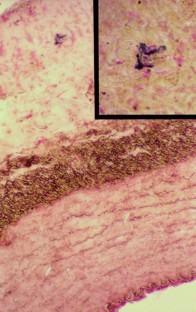

Percutaneous transluminal coronary angioplasty is a routinely used non-surgical revascularization technique for patients with coronary artery disease. Up to 30% of patients undergoing coronary angioplasty develop a renarrowing of treated vessels, called restenosis. Smooth muscle cell proliferation is thought to be an important factor in restenosis; this leads to neointima formation and arterial lumen narrowing. Neointima may be reduced by the transfer of genes encoding proteins with antiproliferative effects. Cecropins are antimicrobial peptides with antiproliferative properties in mammalian cells. Cecropin A is one member of this family of peptides. In this article, a plasmid carrying the gene for the immature form, pre-pro-cecropin A, complexed with liposomes was locally delivered to perivascular tissue in a porcine arterial injury model using a needle injection catheter. Retention of the plasmid in the treated arteries was demonstrated at both 8 and 21 days following application. Transferred plasmid DNA was not detected in any other tissues analyzed. Pre-pro-cecropin A-specific transcripts could also be found in treated arteries. Balloon-injured vessels demonstrated significantly reduced neointima at 21 days in vessels treated with the pre-pro-cecropin A gene compared with neointimal area in those given a control gene (P < 0.05). the needle injection catheter appears to be useful for local intravascular gene delivery. in vivo gene transfer of cecropins may be of therapeutic relevance in restenosis prevention by limiting cell proliferation.